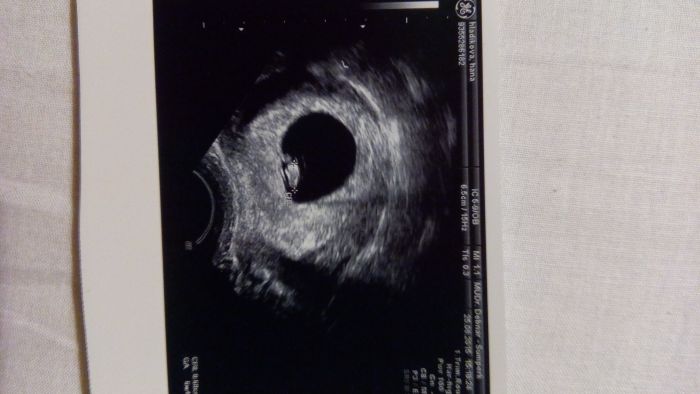

[787413] Hani, tohle je ale moc velké mimčo, na tu metodu podle placenty. To musí být utz z 6.-8.týdne.

Dobře, tak já ní zítra dam :) no taky jsem koukala že je miminko nějaký velký: D

Hani, ze by holcicka?! Ale nevim na kolik se te metode da verit :-o